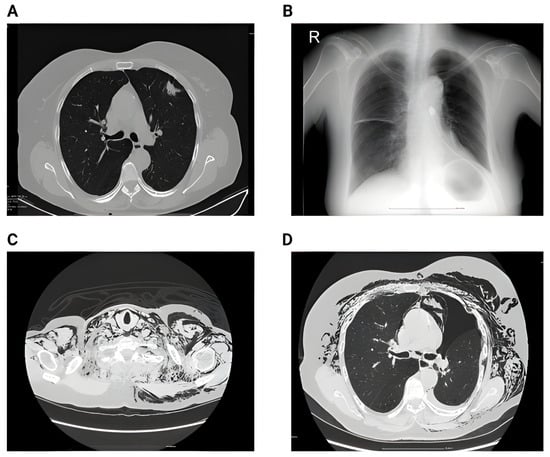

Figure 1 below shows the imagistic changes on x-ray following surgery.

Figure 1. (A) Preoperative chest X-ray showing a pulmonary nodule projected in the middle lobe. No pleural effusion or pulmonary infiltrate. (B) Second postoperative day showing small bilateral pleural effusion, accentuation of the interstitial markings, and a small infiltrate in the right lower lobe; (R = right).

Figure 2. (A) Perioperative RX showing a left superior lobe nodule. No pleural effusion, no atelectasis. (B) Second day postoperative x-ray showing hydropneumothorax with significant fluid in the left pleural cavity, and passive atelectasis. (C) 3rd day postoperative showing effective drainage of the fluid with re-expansion infiltrates and juxta-phrenic peak sign. (D) 6 weeks postoperative showing no pleural effusion, no infiltrates.